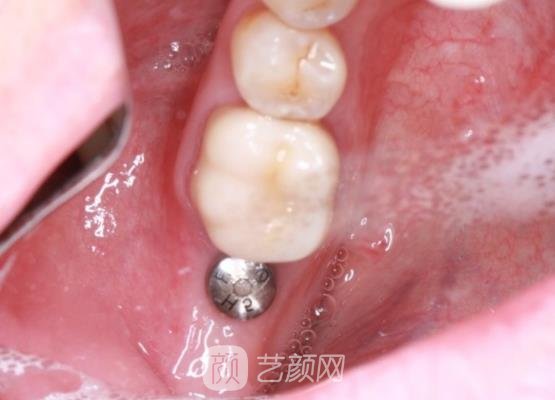

时间过得真快呀,不知不觉已经过去了三个多月,我又早早地来到医院,医生还给我进行了一系列的口腔检查,了解种植体是否出现骨愈合的情况,只要骨愈合之后,就可以在上面安装烤瓷牙冠。

顺利安装上烤瓷牙冠之后,终于可以正常使用我的牙齿了,而且种植牙看起来很真实,一点不像是假牙,现在我也在慢慢练习,使用这颗牙齿,感觉没有很强的异物感,也没有出现过疼痛等异常的情况。